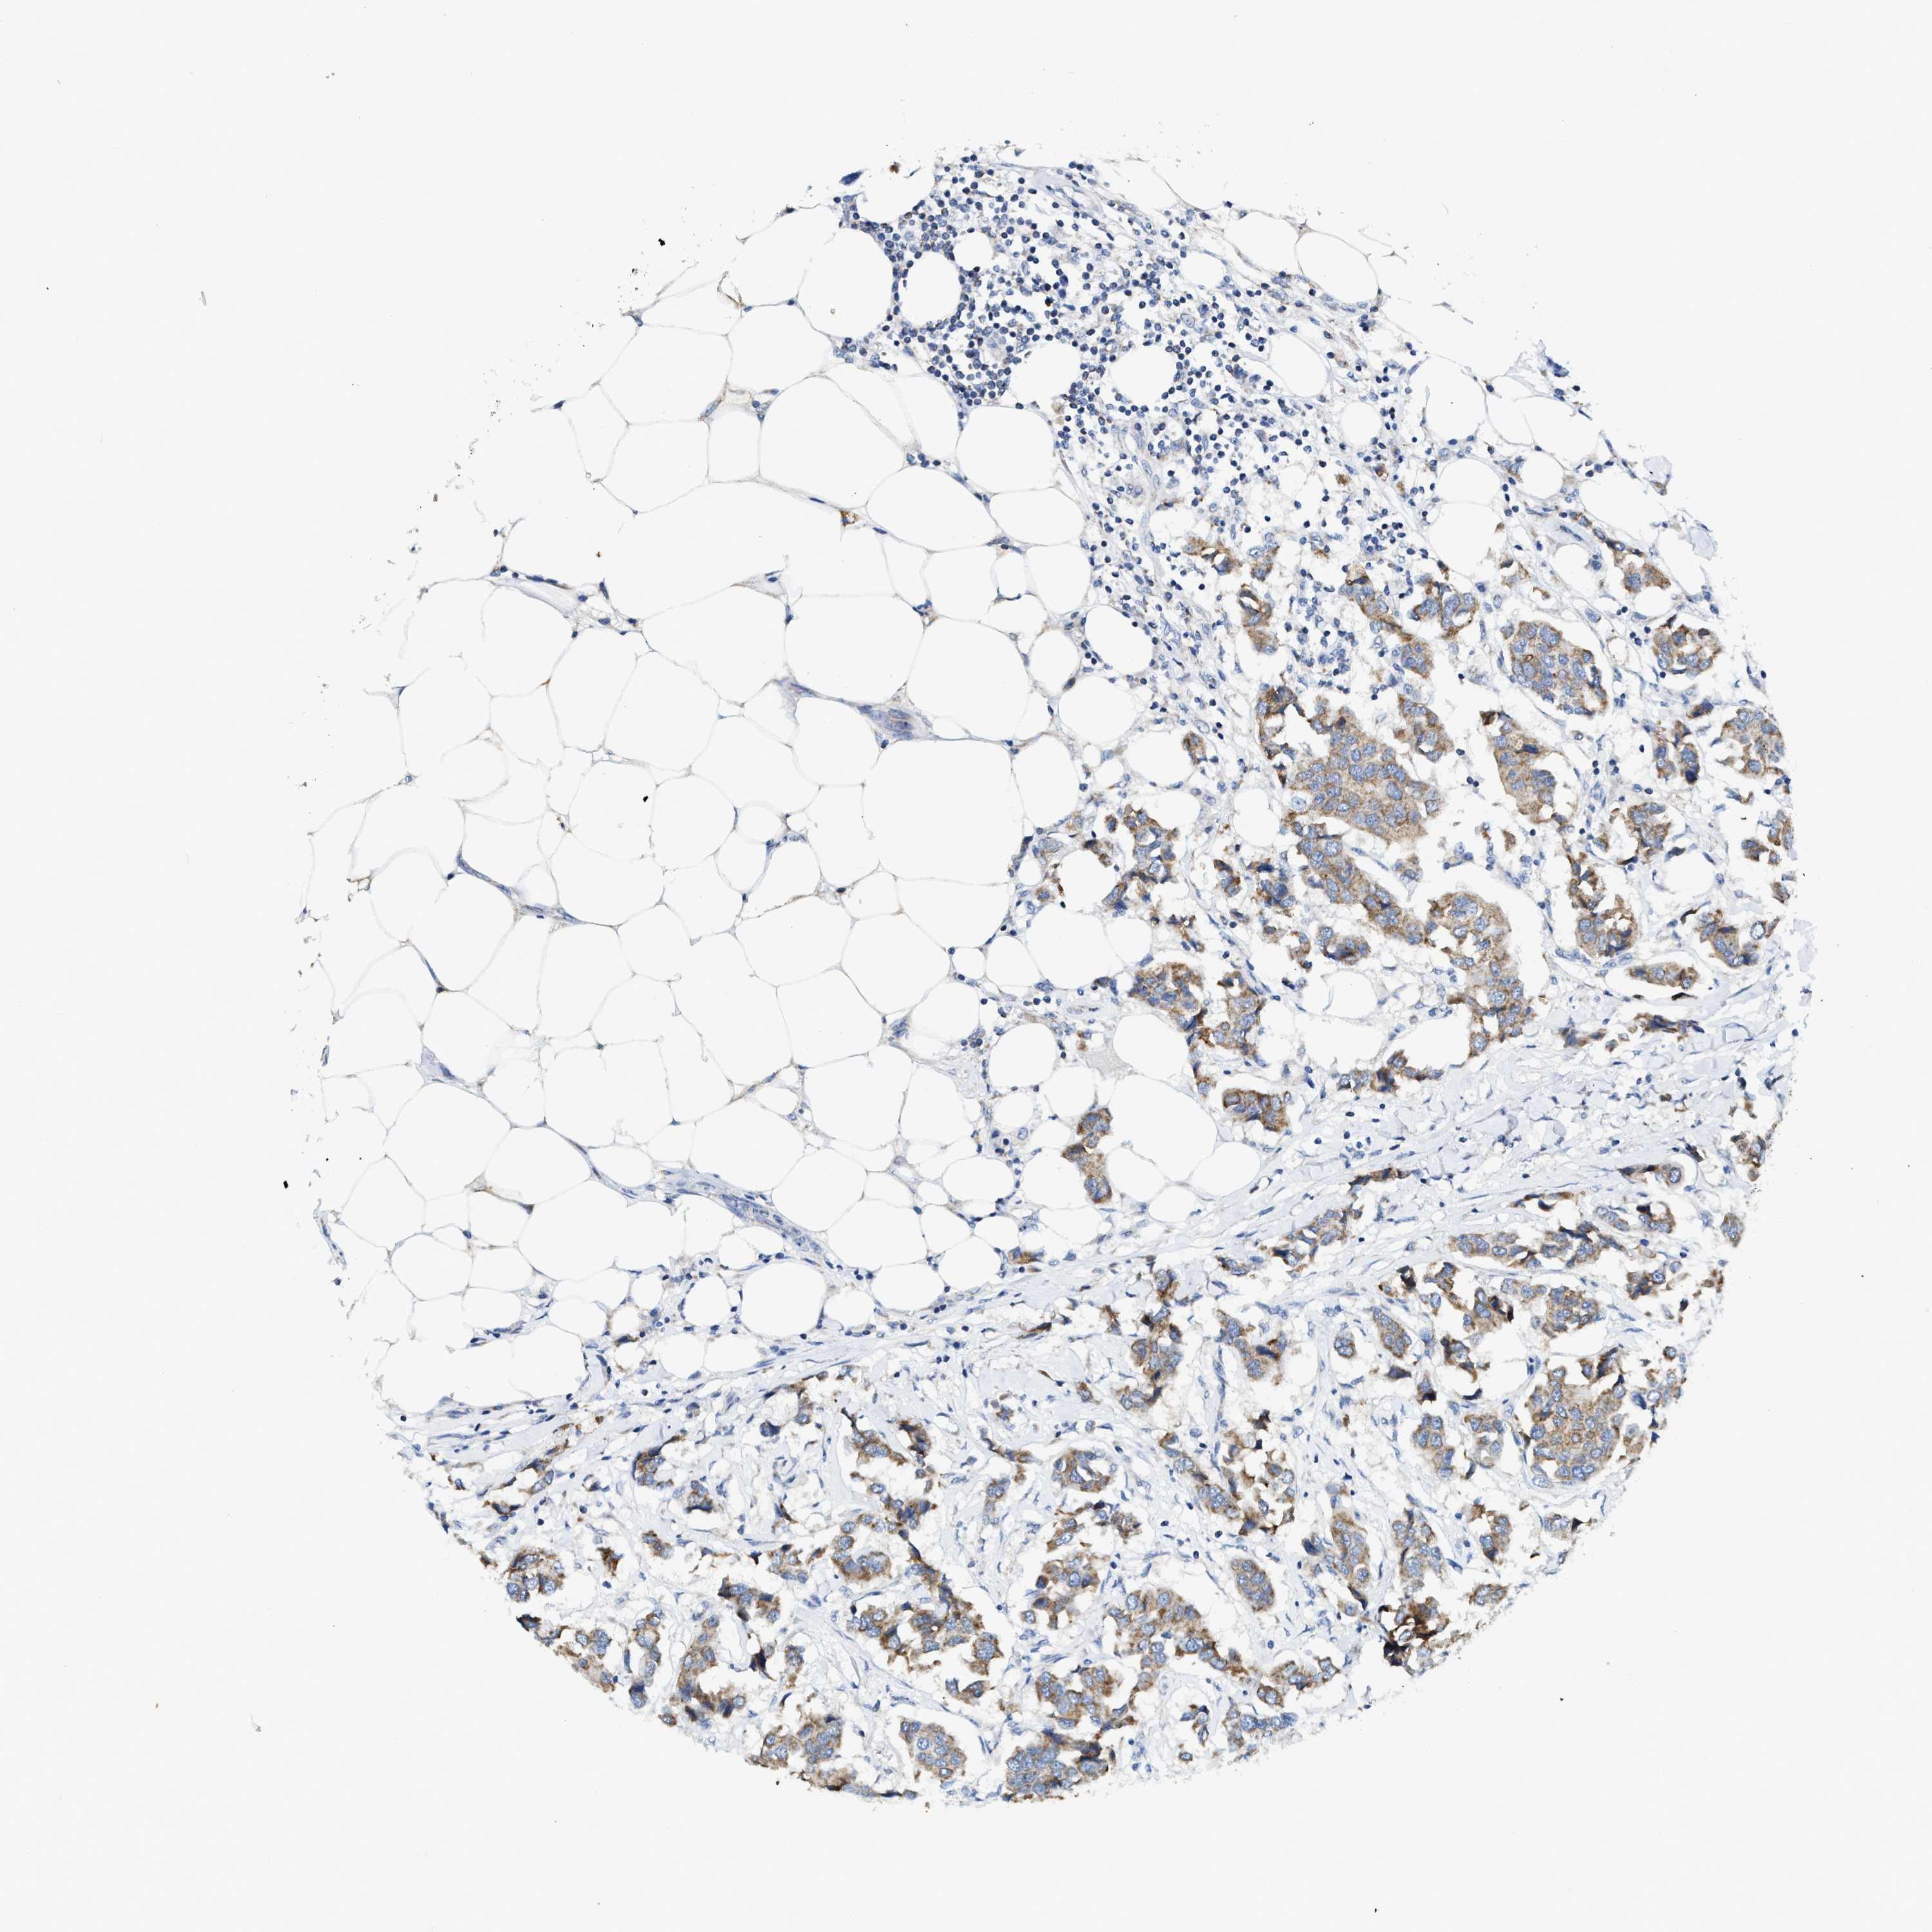

CANCER BREAST CANCER Show tissue menu

BRCA TCGA BRCA VALIDATION PROTEIN EXPRESSION

ANTIBODIES

AND

VALIDATION